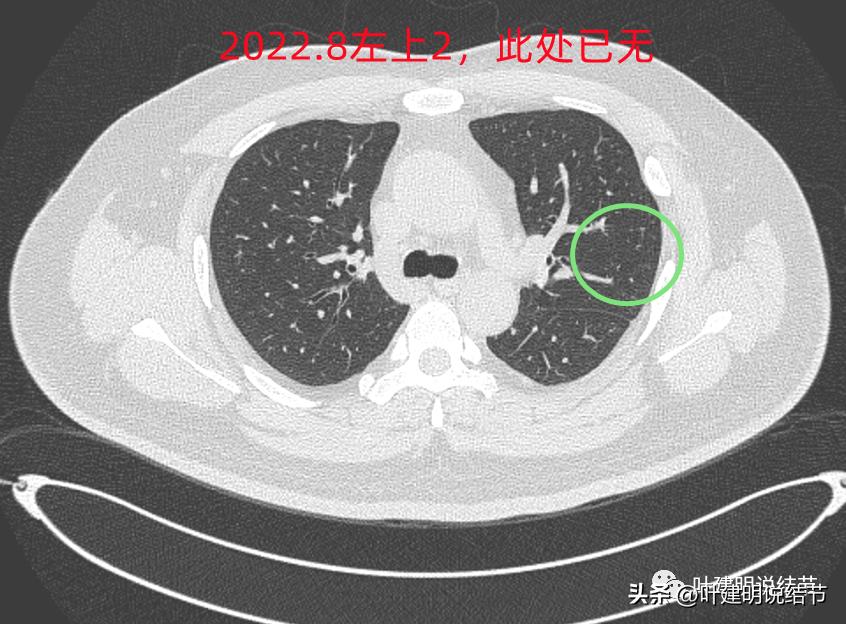

后续再看2022年8月的CT图像,有点惊掉下巴的感觉:

左上叶的病灶1、2、3都没有了!!!完全没有了!那当然说明是炎症性的,居然全部吸收了!

但左上病灶4仍在,形态也没有明显变化,无好转,也无明显进展。这是肿瘤性质的吗?虽然存在2年多了,但因为它的兄弟们都不见了,让我对它认定的肿瘤范畴也产生了怀疑,也许是纤维增生而已呢!